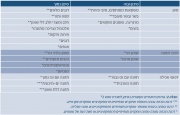

רשימת קבצים

דף מיוחד זה מציג את כל הקבצים שהועלו.

| תאריך | שם | תמונה ממוזערת | גודל | משתמש | תיאור | גרסאות |

|---|---|---|---|---|---|---|

| 13:34, 19 במרץ 2016 | Fetal sex7.png (קובץ) |  |

87 קילו־בייטים | Motyk | 1 | |

| 13:33, 19 במרץ 2016 | Fetal sex6.png (קובץ) |  |

68 קילו־בייטים | Motyk | 1 | |

| 13:29, 19 במרץ 2016 | Fetal sex5.png (קובץ) |  |

91 קילו־בייטים | Motyk | 1 | |

| 11:47, 19 במרץ 2016 | Fetal sex4.png (קובץ) |  |

149 קילו־בייטים | Motyk | 1 | |

| 09:17, 19 במרץ 2016 | Fetal sex3.png (קובץ) |  |

67 קילו־בייטים | Motyk | 1 | |

| 09:16, 19 במרץ 2016 | Fetal sex2.png (קובץ) |  |

80 קילו־בייטים | Motyk | 1 | |

| 09:12, 19 במרץ 2016 | Fetal sex1.png (קובץ) |  |

74 קילו־בייטים | Motyk | 1 | |

| 15:15, 17 במרץ 2016 | Pre-implantation2.png (קובץ) |  |

219 קילו־בייטים | Motyk | 1 | |

| 13:22, 17 במרץ 2016 | Pre-implantation1.png (קובץ) |  |

203 קילו־בייטים | Motyk | 1 | |

| 10:09, 17 במרץ 2016 | Cervical pregnancy3.png (קובץ) |  |

39 קילו־בייטים | Motyk | 1 | |

| 10:09, 17 במרץ 2016 | Cervical pregnancy2.jpg (קובץ) |  |

17 קילו־בייטים | Motyk | 1 | |

| 10:08, 17 במרץ 2016 | Cervical pregnancy1.jpg (קובץ) |  |

37 קילו־בייטים | Motyk | 1 | |

| 14:45, 14 במרץ 2016 | רובוט-דה-וינצי1.jpg (קובץ) |  |

116 קילו־בייטים | Motyk | 1 | |

| 13:05, 14 במרץ 2016 | Hypergastrinemia3.jpg (קובץ) |  |

227 קילו־בייטים | Motyk | 1 | |

| 12:52, 14 במרץ 2016 | Hypergastrinemia2.jpg (קובץ) |  |

121 קילו־בייטים | Motyk | 1 | |

| 12:38, 14 במרץ 2016 | Hypergastrinemia1.jpg (קובץ) |  |

108 קילו־בייטים | Motyk | 1 | |

| 18:09, 12 במרץ 2016 | Tarsal tunnel1.jpg (קובץ) |  |

119 קילו־בייטים | Motyk | 1 | |

| 15:14, 10 במרץ 2016 | Smoking cessation3.jpg (קובץ) |  |

226 קילו־בייטים | Motyk | 1 | |

| 14:55, 10 במרץ 2016 | Smoking cessation2.jpg (קובץ) |  |

72 קילו־בייטים | Motyk | 1 | |

| 13:54, 10 במרץ 2016 | Smoking cessation1.jpg (קובץ) |  |

111 קילו־בייטים | Motyk | 1 | |

| 09:48, 10 במרץ 2016 | Β-Galactosidase1.png (קובץ) | 3 קילו־בייטים | Motyk | 1 | ||

| 14:19, 7 במרץ 2016 | פרמידה בריאטרית.png (קובץ) |  |

229 קילו־בייטים | Motyk | 1 | |

| 12:32, 3 במרץ 2016 | Breastcancer.jpg (קובץ) |  |

167 קילו־בייטים | דנה לוי | 1 | |

| 19:18, 2 במרץ 2016 | Bariatric4.png (קובץ) |  |